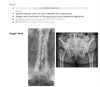

• πŸ–ΌοΈ Radiographic Hallmarks including bamboo spine and dagger spine